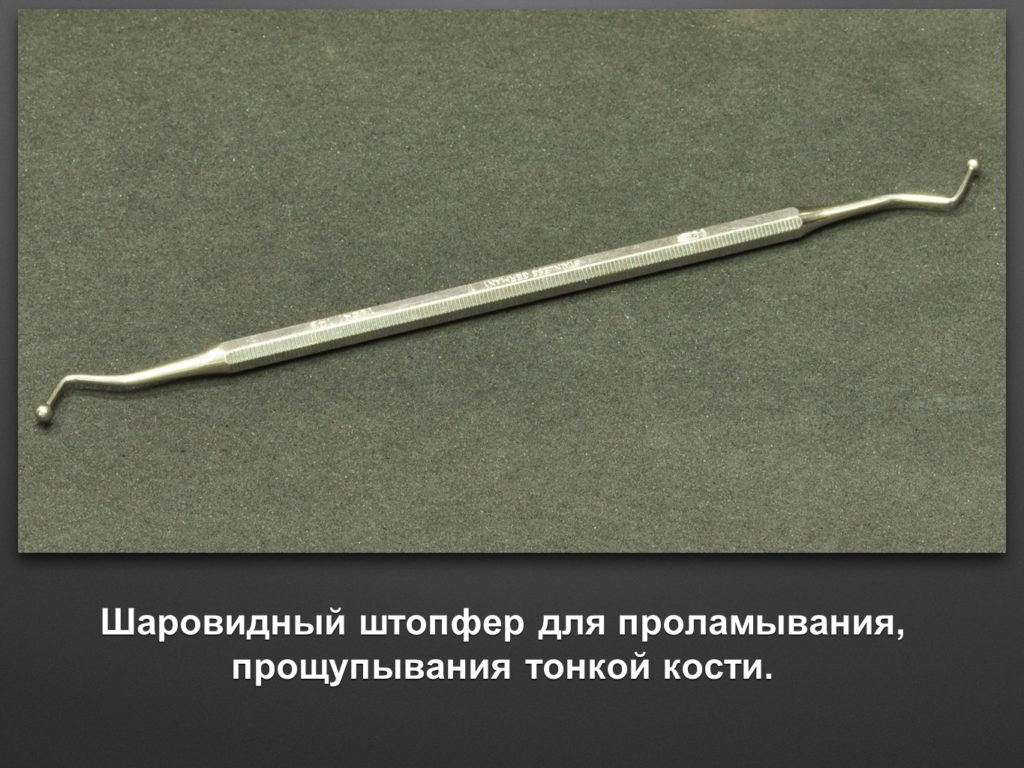

"Выстраданные" наборы инструментов

Все ниже перечисленные инструменты можно приобрести на сайте kohlermed.ru или связаться с нашим менеджером по тел 499-5179401

Все ниже перечисленные инструменты можно приобрести на сайте kohlermed.ru или связаться с нашим менеджером по тел 499-5179401